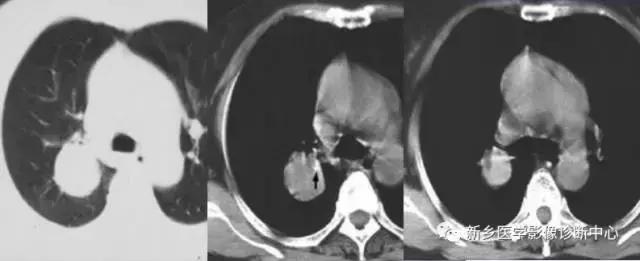

单发胸膜间皮瘤

常发于胸壁腋缘,单发、多发良性,无症状或局部钝疼。圆形或半球形密度影,基底位于胸膜,与胸壁成钝角,密度均匀。

4个不同的胸膜间皮瘤: